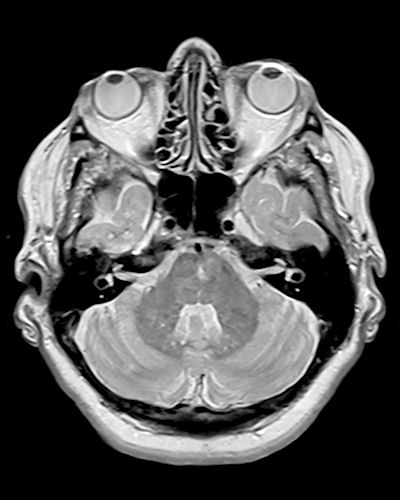

Mark the lesion in this scan